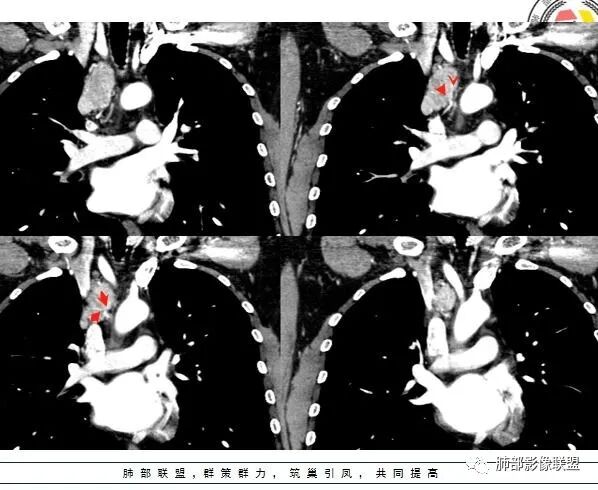

动脉期显著强化,结节呈“门状结构”附近多发子灶——CD!

中年男性右上纵隔椭圆形软组织肿块,边界清,密度均匀,明显均匀强化(峰值在动脉期),周围见小血管影进入及有小淋巴结,考虑CD>副节。

右前中纵隔软组织肿块,有钻缝生长特点,边界清,周围脂肪血管未见受侵,增强动脉期明显强化,明显持续强化,内部及周围见血管,周围见小淋巴结,考虑CD,鉴别淋巴瘤,强化不支持;胸腺瘤,不常见部位,形态也不支持;副节瘤,这么大肿块坏死囊变应很明显;神经内分泌肿瘤,强化太均匀、生化不支持,周围结构改变也不符合;神经鞘多有AB区,渐进性强化!

纵膈内上腔静脉内后方肿块,边缘清晰,形态不规则,周围可见多发小淋巴结,明显强化。纵膈内强化明显的常见有CD,异位甲状腺,副节瘤,血管瘤。异位甲状腺平扫密度高一些,钙化常见,不符。副节瘤好发生于后纵膈、主动脉旁、肺动脉旁、心包内,而且容易坏死,一般沿神经节分布,纵径大于横径。综合考虑:CD>副节瘤。